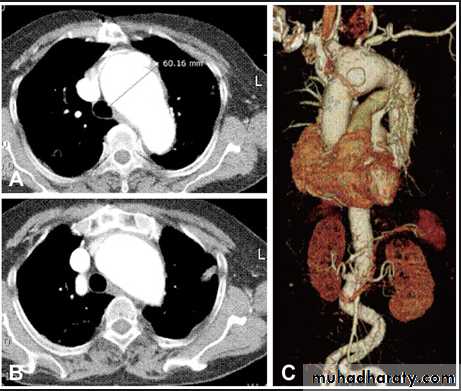

Thymoma.

A chest x-ray (A) reveals an unusual contour over the left hilum (arrows). That the hilum is not obscured (no silhouette sign) indicates that the mass must either be in front of or behind the hilum. A computed tomography scan (B) reveals a soft tissue mass (arrow) just to the left of the aorta. This is the most common location of a thymoma.

chest practice

Mediastinal teratoma. A chest x-ray (A) shows a large upper right mediastinal mass (arrows), but no specific internal structure is apparent. A computed tomography scan (B) reveals that the mass contains multiple types of tissue elements including fat (dark), soft tissue (gray), and calcium (white). This is essentially diagnostic of a teratoma.